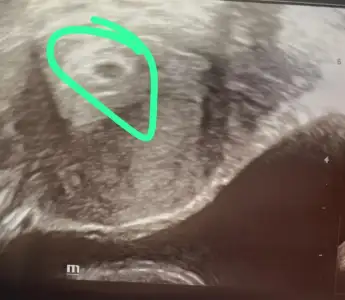

5+1 de keseyi gördüm bende fotoğrafı var mı senin benim böyle içinde bişeyler görünüyor bir bak istersen sanırım aynı zamanda kalmışız bende 6+3m

Eklentiler

• 04897cab-7095-4c19-8dbe-7f5947813237.webp

04897cab-7095-4c19-8dbe-7f5947813237.webp

29,1 KB · Görüntüleme: 30